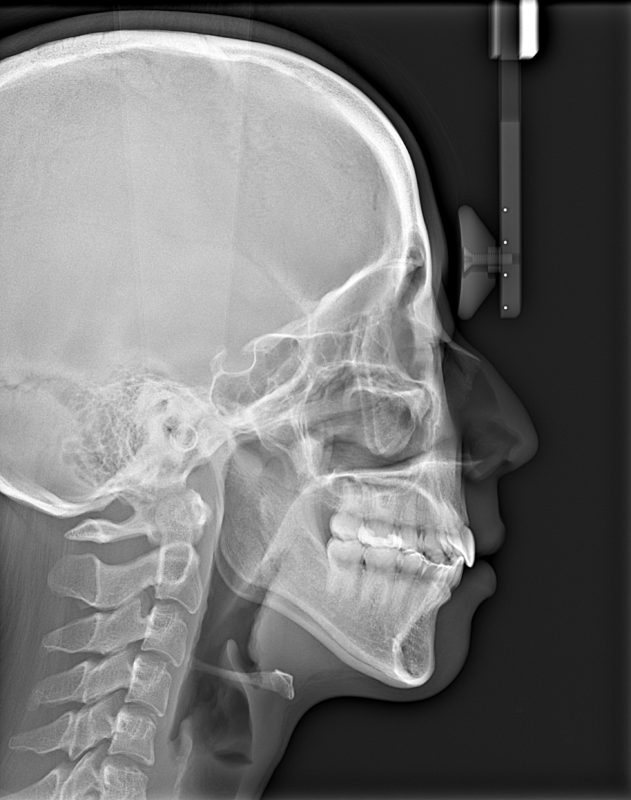

横顔のレントゲン(側面セファロ)を撮影し、同じ年齢の歯並びが良い人のデータと比較し、上あご下あごの前後的位置を確認します。成長期のうちに上下のあごのバランスを整えておくことで、二期治療での抜歯が必要なくなったり、将来的な外科矯正のリスクが少なくなったりするなど、たくさんのメリットがあります。